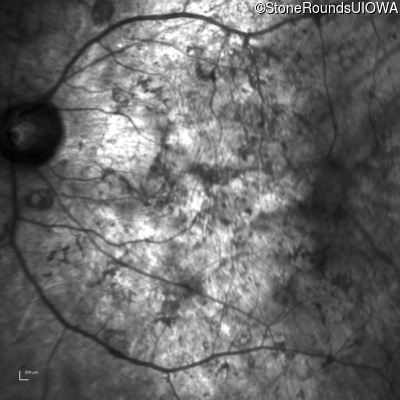

Infrared Fundus Photograph - Right - Hand Motion sc

Exemplar